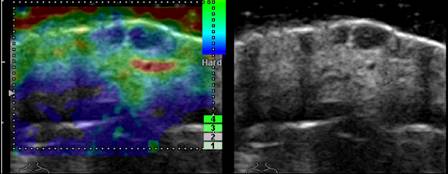

An elastogram (left) and ultrasound image (right)

showing squamous cell carcinoma of the skin.

For the study, researchers used an ultra high-frequency ultrasound

system to image 40 patients with a variety of malignant and nonmalignant,

or benign, skin lesions. Malignant tumours included squamous cell

carcinoma, basal cell carcinoma and melanoma. Benign lesions included

dermatofibroma, a noncancerous growth containing scar tissue, and lipoma,

a noncancerous tumour composed of fatty tissue.

The researchers calculated the ratio of elasticity between normal

skin and the adjacent skin lesion, and used laboratory analysis to

confirm their diagnoses. Cystic lesions, which are not malignant,

demonstrated high levels of elasticity, while malignant lesions were

significantly less elastic. The elasticity ratio of normal skin to the

various skin lesions ranged from 0.04 to 0.3 for cystic skin lesions to

above 10.0 for malignant lesions.